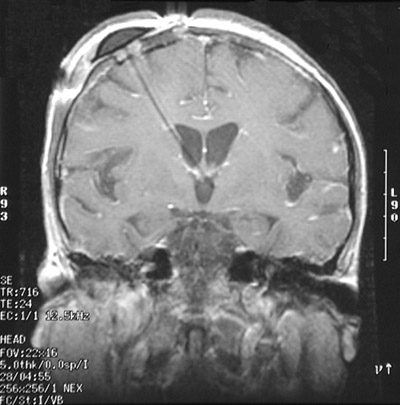

| In the coronal view above and the sagittal view below with these T1 weighted MRI scans can be seen an Ommaya reservoir placed under the scalp with catheter extending into the ventricle in a patient with a carcinoma metastatic to the meninges. Such a reservoir provides a means for delivering chemotherapeutic agents in high concentration. |